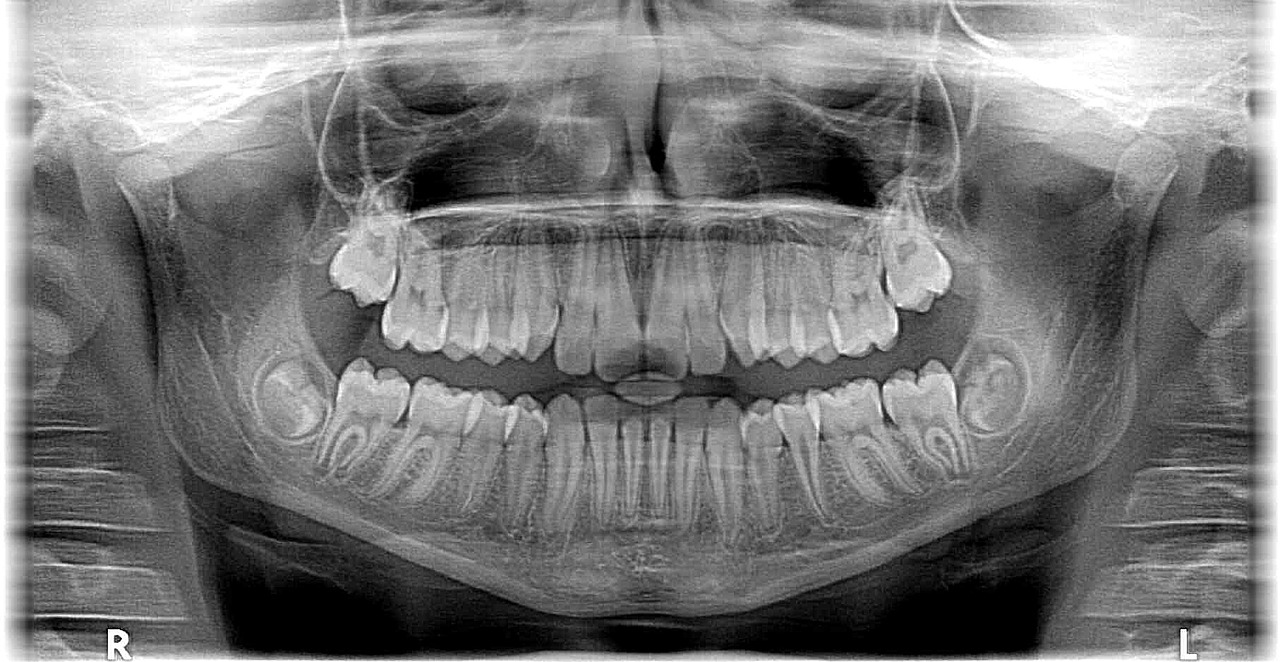

그리고 위 사진과는 다르게 치아가 똑바르게 나지않고

기울거나 누워있는 경우에는 발치를 하는 것이 바람직하다고 합니다.

위 사진은 제 치아사진입니다.

사진으로 보는 왼쪽이 사랑니가 누워있는데

이렇게 되면 사랑니가 어금니를 밀어낸다고하더라고요.